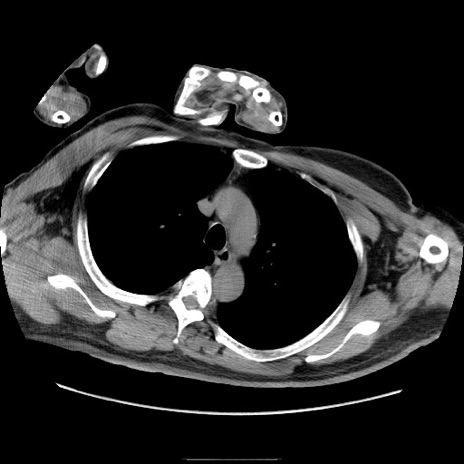

冠状断像

【症例】50歳代男性

【主訴】腹痛

【現病歴】AVMからの被殻出血のため回復期リハ病棟入院中。 本日午後3時頃急に下腹部痛が出現した。

【既往歴】AVM、被殻出血、虫垂炎、高血圧

【身体所見】意識晴明、左半身不全麻痺、会話の理解は良好、36.5°C、腹部:膨隆、全体に板状硬、下腹部正中に圧痛点あり、反跳痛-、筋性防御不明、右下腹部にope scar

【データ】WBC 9400、CRP 0.06